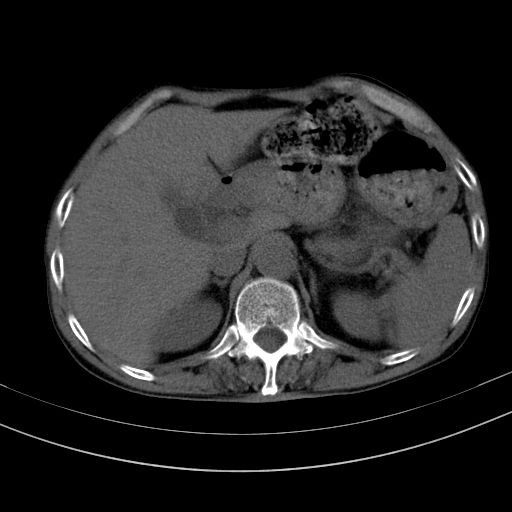

以下是引用dyqct在2010-1-9 17:56:00的发言:[br]考虑:1.双肾囊肿,左肾积水结石、旋转不良。[br] 2.右侧腹直肌血肿或纤维瘤。[br]肠道准备不好。做个增强。